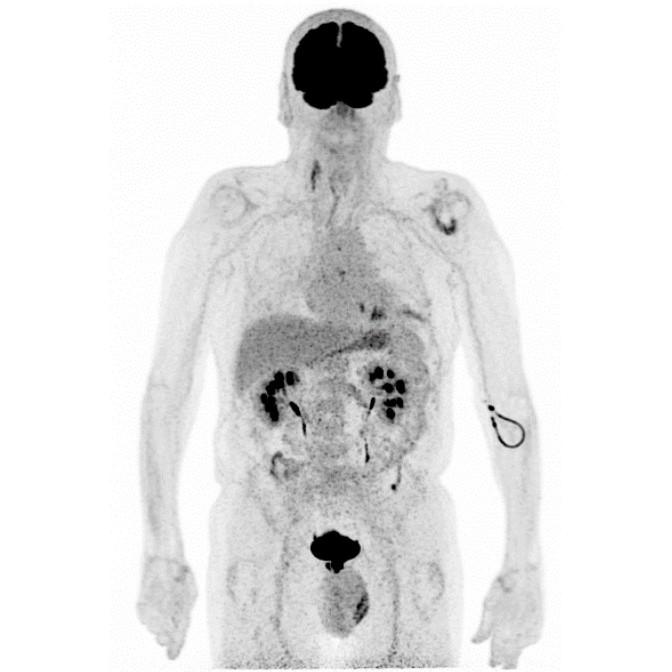

Partial nml and melanoma PET scan